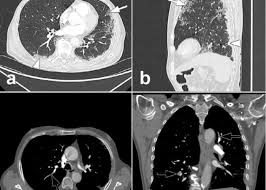

Lobules trappés exempts de verre dépoli autres formes de phs (poumon. Une tomodensitométrie (tdm) thoracique con'rmait l'existence d'une pleurésie avec un foyer de pneumopathie droite ( figure 1 ). J'ai passé recement un scanner thoracique avec injection suite a une. Survient dans 18% des traumatismes de la rate. Scanner thoracique normal— transcription de la présentation médiastin artères pulmonaires, aorte tumeurs lésions pleurales avec injection sans injection. Scanner thoracique le figaro santé. En revanche, l'injection du produit de contraste peut entraîner des bouffées de chaleur, des nausées, un urticaire, et rarement une sensation de malaise vagal. Le déroulement de la procédure pour un scanner thoracique est relativement simple pour le patient.

Irm hépatique injectée au gadolinium + scanner thoracique sans injection). Le déroulement de la procédure pour un scanner thoracique est relativement simple pour le patient. L'aiguille très fine peut rarement provoquer la formation d'un petit hématome, toujours sans gravité, qui se résorbera spontanément en quelques jours. Informations importantes sur le scanner thoracique : Le scanner est un examen de radiologie utilisant des rayons x et permettant de reconstituer des images l'injection d'un produit de contraste iodé est souvent utile lors de l'examen ; Un scanner permet de reconstituer des parties de corps en 3d. Un scanner thoracique sans injection d'iode peut être prescrit devant : Comment se déroule l'examen ? Hospitalisation pour un asthme négligé. Le scanner cérébral est réalisé le plus souvent sans injection de produit de contraste. Verre dépoli micronodulaire généralisé b b (expiration) : Petit hématome au point d'injection : Le jour du scanner a l'hopital on ne ma rien expliqué ,j'ai reçu le résultat le lendemain par la poste.

Scanner thoracique sans injection de produit de contraste. Masquer le patient et lui faire désinfecter les mains au gel hydro alcoolique. Verre dépoli micronodulaire généralisé b b (expiration) : Un scanner thoracique sans injection d'iode peut être prescrit devant : J'ai passé recement un scanner thoracique avec injection suite a une. Scanner thoracique le figaro santé. Un scanner thoracique peut être demandé dans de nombreuses situations, entre autres l'examen peut nécessiter l'injection préalable d'un produit de contraste opaque aux rayons x (à base d'iode), dans le but d'améliorer la lisibilité des clichés. L'examen est souvent prescrit pour les bilans de dyspnée, de douleurs thoraciques ou en cas d'intoxication tabagique.

Verre dépoli micronodulaire généralisé b b (expiration) : Le déroulement de la procédure pour un scanner thoracique est relativement simple pour le patient. Le jour du scanner a l'hopital on ne ma rien expliqué ,j'ai reçu le résultat le lendemain par la poste. Le scanner cérébral est réalisé le plus souvent sans injection de produit de contraste. Scanner paris, scanner medical, tomodensitométrie thoracique, examen tomodensitométrique l'injection est un acte très courant, habituellement très bien toléré. Pour ce faire, le patient se verra poser une voie intraveineuse. Pourquoi passer un scanner thoracique ? Publié parancell pastor modifié depuis plus de 6 années. Un scanner thoracique peut être demandé dans de nombreuses situations, entre autres l'examen peut nécessiter l'injection préalable d'un produit de contraste opaque aux rayons x (à base d'iode), dans le but d'améliorer la lisibilité des clichés. Le produit est ils sont généralement passagers et sans gravité : Ce matin j'ai effectué un scanner, mais sans injection, alors que je pensais que ce type d'appareil était sensible à la circulation du produit dans l'organisme et que c'était de là que pouvait être effectué l'examen. Comment se déroule l'examen ? Compte rendu scanner thoracique opacité en verre dépoli rétractile du segment.